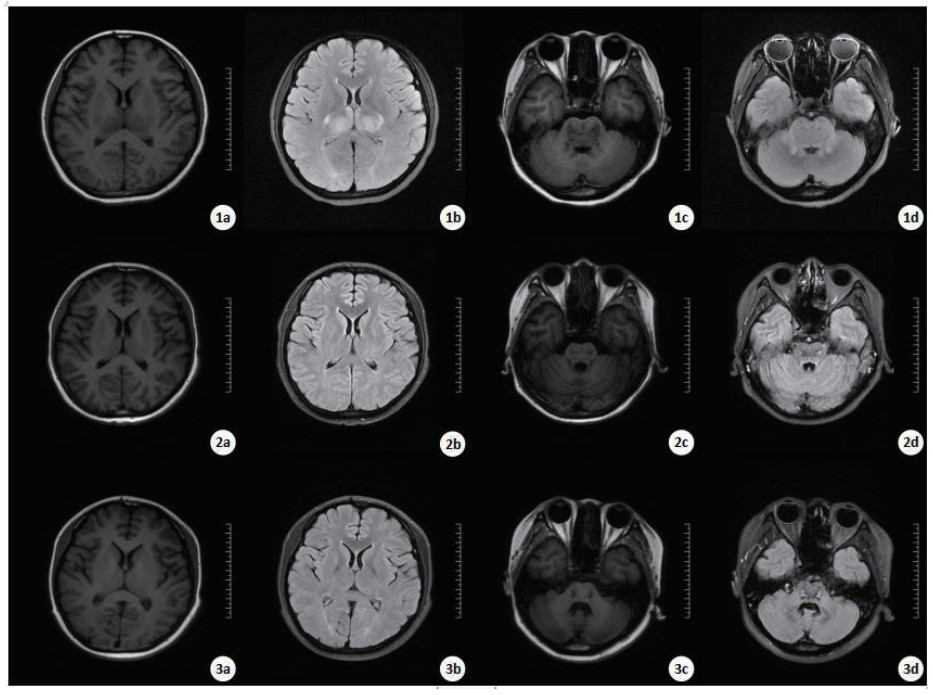

病例2:患者女,26岁,以“口服敌草快50 mL 15 h”代主诉入院,急至当地医院给予洗胃、导泻,后出现头晕、头痛,双下肢麻木,伴不自主抽搐,体格检查:体温37.2℃,脉搏68次/min,呼吸22次/min,血压166/102 mmHg,入院查体未见明显异常。完成实验室检查,血常规WBC 25.12×109/L、RBC 3.26×1012/L、PLT 132×109/L,N% 96.6%;肝功能:AST 284 U/L,ALT 237 U/L;肾功能:Cr 224μmol/L,eGFR 25.327 mL/min/1.73 m2; 血气分析:pH 7.48,PO2 131 mmHg, PCO2 17.3 mmHg,HCO3- 21.00 mmol/L, Lac 1.4 mmol/L。给予导泻、护胃,血液透析、血液灌流,糖皮质激素等治疗同前。入院第2天出现神志模糊、烦躁,第3天出现言语错乱,第4天出现昏迷、GCS评分4分(E1V1M2), 查头颅CT: 双侧基底节区、丘脑、脑干密度弥漫性减低。第7天查头颅MRI(如图 2)。考虑中毒性脑病,给予甘露醇降颅压,依达拉奉、维生素B1、甲钴胺、醒脑静等营养神经、促醒药物应用。第34天患者清醒,出现精神行为异常,智力下降、狂躁、暴饮暴食,第60天复查MRI(如图 2): 桥脑及中脑可见对称性斑片状长T1长T2信号影。左侧额叶、右侧顶叶见少许点片状稍长T2信号影。双侧乳突区见斑片状高信号。第105天MRI: 较前变化不大。患者精神行为异常较前未见明显变化,MOCA评分:26分,MMSE(简易智能精神状态量表)评分:29分,均正常(现仍随访中)。

| 入院第7天的MRI显示,T1WI(1a和1c)、T2WI(1b和1d): 胼胝体压部、双侧丘脑、双侧基底节区、脑干异常信号。第60天、第105天MRI显示,T1WI(2a和2c、3a和3c)、T2WI(2b和2d、3b和3d): 左侧额叶、右侧顶叶见少许点片状稍长T2信号影,黑水像呈稍高信号。桥脑及中脑可见对称性斑片状长T1长T2信号影,黑水像中心呈高信号,边缘环绕低信号。 图 2 病例2的MRI结果 Fig 2 MRI results of Case 2 |

而病例2未出现癫痫样症状发作,出现昏迷的时间也较晚,影像学检查未见明显脑水肿表现。这种差异性的表现考虑与特定的神经传导通路相关,具体损伤的机制仍在探索中。此外,我们观察到存活的3例患者均为年轻女性,平均年龄19.3岁(26岁、14岁、18岁),DQ导致的神经毒性表现是否与年龄和性别有关,因本研究观察到的病例数较少、暂不能得出有效结论。但有动物实验[24]表明,雌性大鼠比雄性大鼠更容易耐受DQ所致的氧化应激反应。Djukic等[22]用非选择性一氧化氮合酶抑制剂(NG-nitro-L-arginine methylester,L-NAME)预处理可降低DQ的神经毒性作用,并减少应激/亚硝化对DQ诱导的神经毒性的反应。考虑到动物实验中DQ所致脑区损害的差异较大、与人体神经系统损伤有所不同,可能与脑组织血管供应相关,L-NAME在人体内是否存在相同的保护机制仍有待探究。